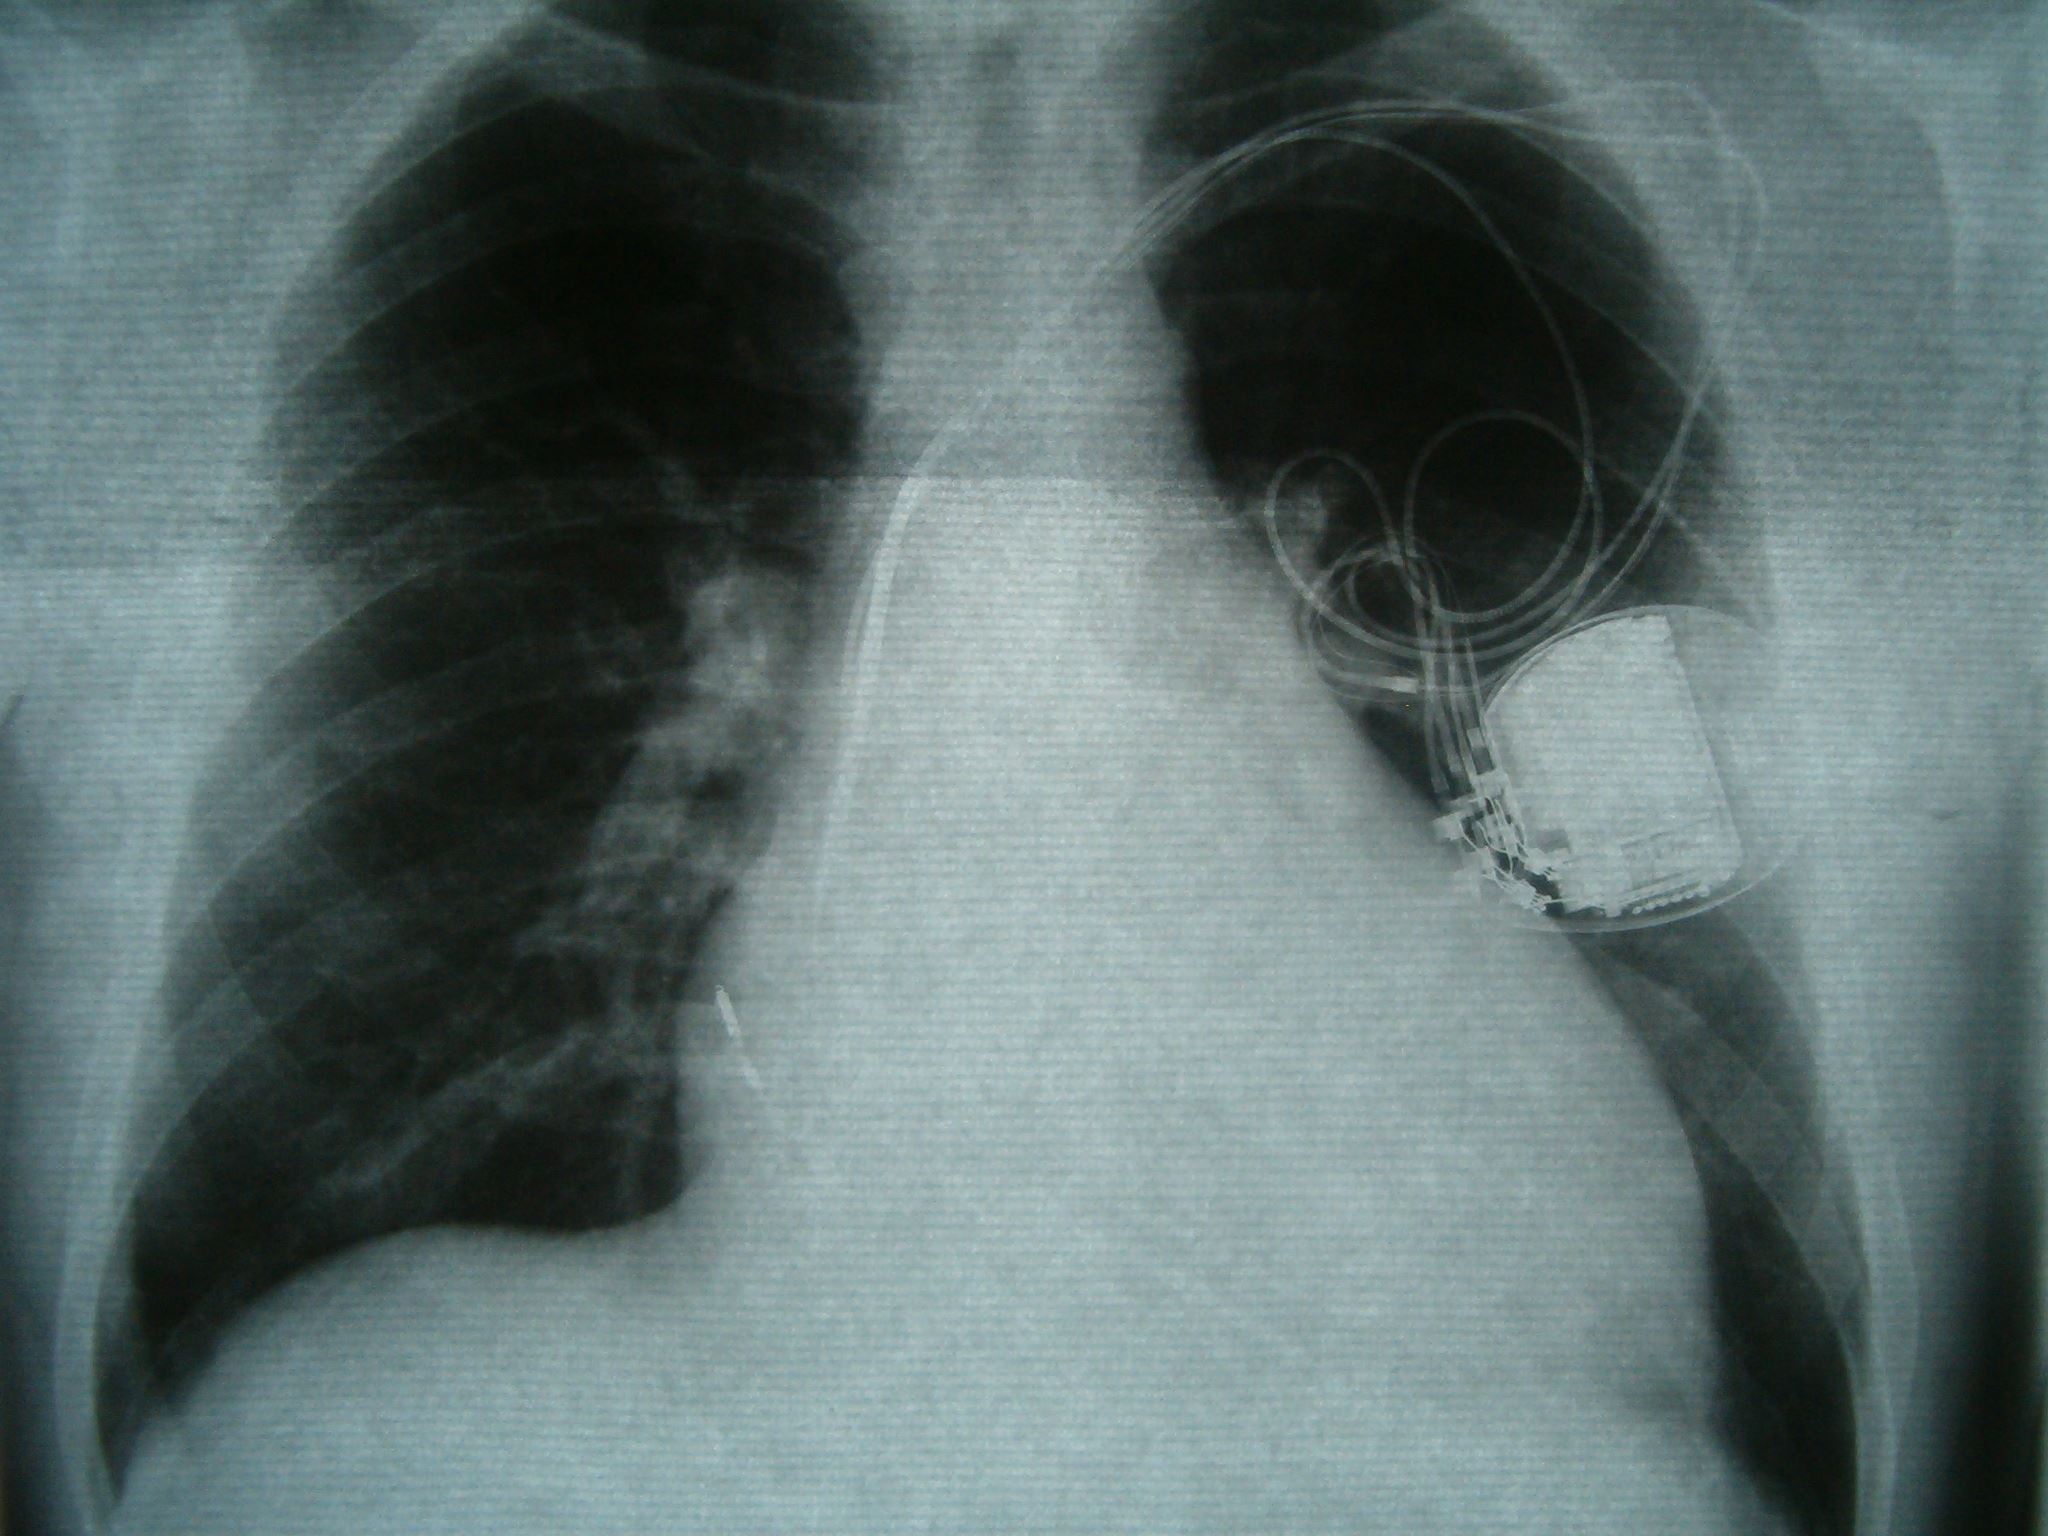

A heart pump implant called the HeartWare Ventricular Assist Device, or HVAD was meant to give patients time to find transplants. It was first introduced into the U.S. market in 2012.

The implant was placed in approximately 19,000 patients between 2012 and this June when Medtronic removed the device from the market.